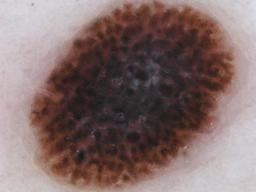

Melanoma and Nevus Dermoscopy Images with Confirmed Histopathological Diagnosis

- Name: Melanoma and Nevus Dermoscopy Images with Confirmed Histopathological Diagnosis

Description:

Collection defined by Dr. Jorge A. Rios-Duarte for a research project.